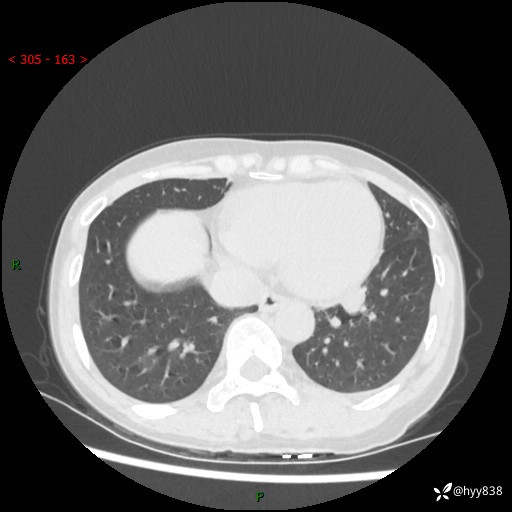

【患者信息】:55岁/女

【主诉】:咳嗽咳痰半月,发现肺占位2天

【现病史及既往史】:患者半月前出现咳嗽咳痰,伴头晕胸闷、无发热气喘。于当地医院住院行抗感染治疗1周(具体药物不详),后咳嗽减轻,但仍未完全缓解,复查胸部CT示:左肺下叶1.8*1.2结节软组织影。为求进一步诊治来我院,门诊以“肺占位”收入院。 自患病以来,精神、饮食、睡眠尚可,大小便正常,体力体重无明显减少。

【检查】:胸部CT平扫+增强

各期CT值:40hu 57hu 49hu